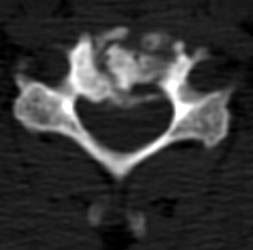

61 y.o male, s/p c4-5 discectomy and interbody fusion for myelopathy.

Initial post-operative films show bone graft intact, with mildly

prominent pervertebral soft tissues, as expected in the immediate post-operative

period. |

8 months later, the follow-up films demonstrate lucency at the

graft site worrisome for resorption. Figure _. Axial CT examination, without

contrast. |

The axial images, and the sagittal reconstructions (not

shown) show some central lucency in the region of graft placement,

suggesting partial resorption of the graft material. |